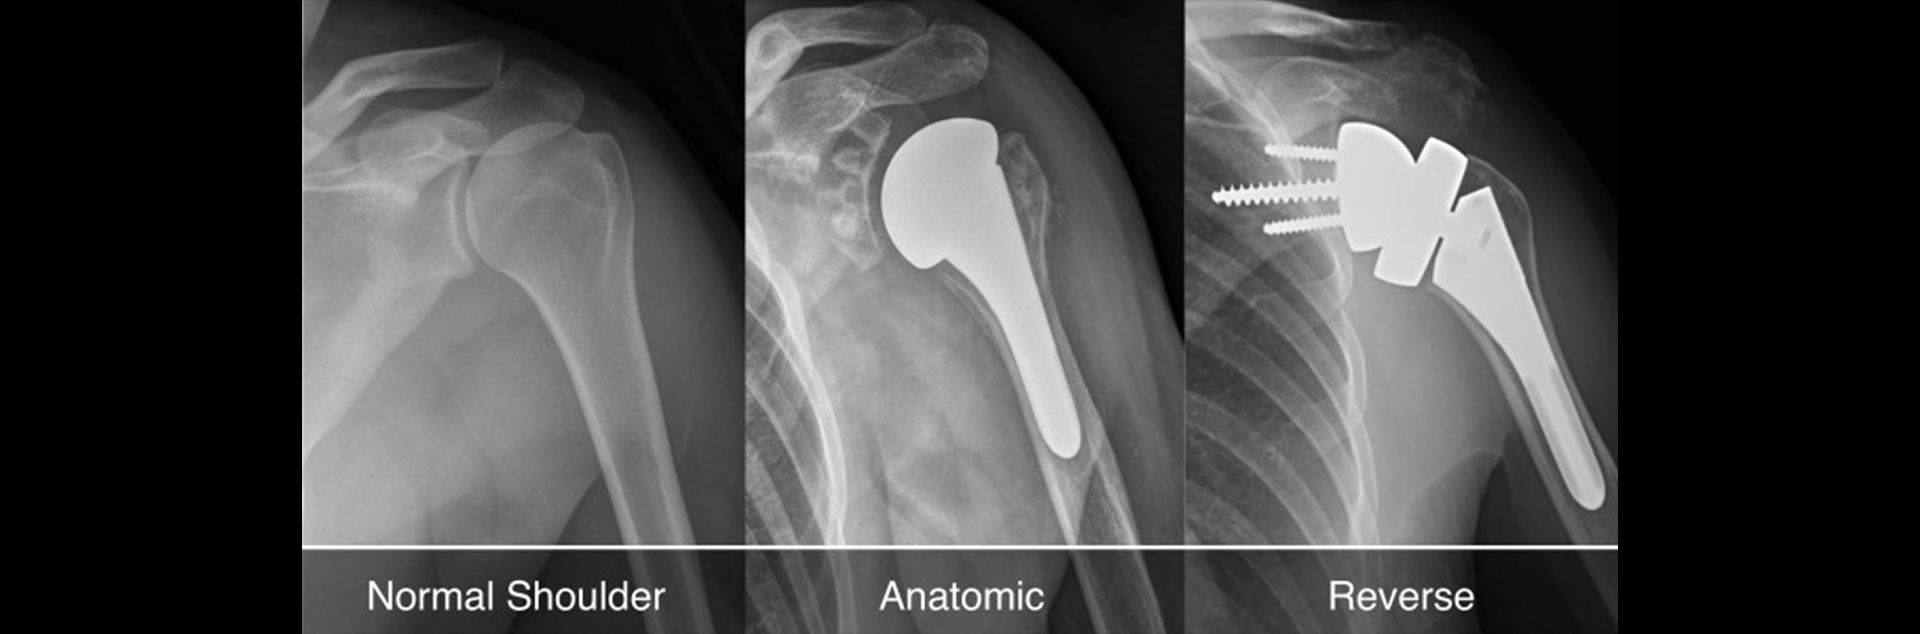

Total shoulder replacement surgery is designed to relieve the pain and dysfunction caused by osteoarthritis, rheumatoid arthritis, or other degenerative conditions of the shoulder. The procedure involves removing the damaged parts of the shoulder joint and replacing them with artificial components. This includes replacing both the humeral head (ball) and the glenoid (socket) with prosthetic parts. The goal of the surgery is to alleviate pain, improve mobility, and restore function to the shoulder.

2. Removal of Damaged Tissue: The damaged humeral head (ball) is removed, and the bone is hollowed out to prepare for the prosthetic.

3. Humeral Prosthesis: A metal ball with a stem is inserted into the humerus and secured with cement.

4. Glenoid Prosthesis: The damaged part of the socket is prepared, and a plastic glenoid component is fixed into the scapula.